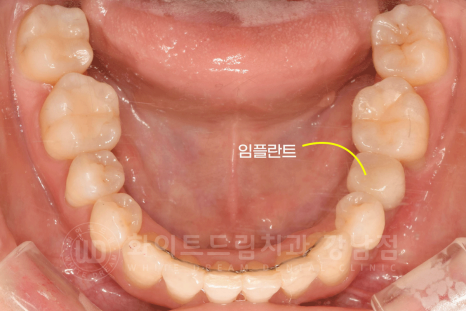

환자분의 초진 구내 사진입니다.

치아의 틀어짐과 덧니가 심한 상태였고, 몇몇 치아는 교합이 반대로 물리는 치열이었고 상/하악 치아의 교합은 좋은 상태였습니다.

치아의 틀어짐 외에도 문제가 하나 더 있었는데요.

35번 치아가 상실되었고, 상실된 지 시간이 오래되어 주변 치아들이 다 쓰러진 상태였습니다.

그리고 골 소실도 심한 상태였죠.

교정 전 :15.08.01 / 교정 중 공간 체크 일자 : 17.02.28

교정 전 구내 사진과 비교해 보면,

악궁과 치열의 변화는 물론 쓰러졌던 치아들이 올바른 자리를 찾아간 것이 확인됩니다.

쓰러진 치아들로 공간이 없었던 35번 치아의 빈자리가 확보되었습니다. ^^